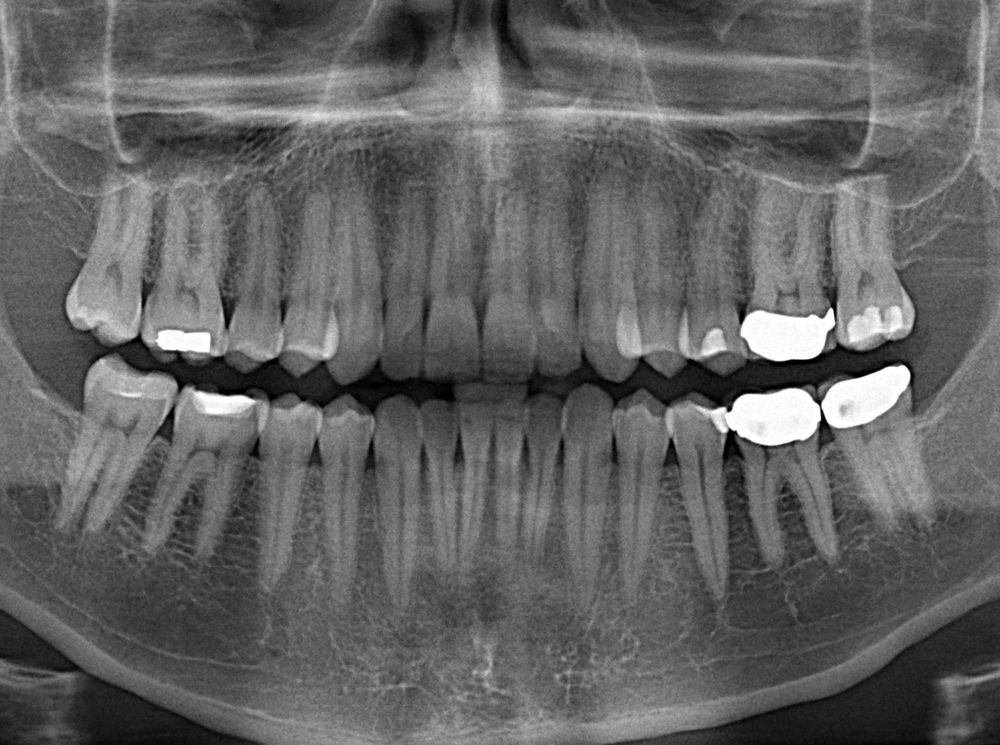

Dentists treat hundreds of millions of cavities each year by drilling out the decay and putting in a filling.

But 10 to 15 percent of those fillings fail, says Adam Celiz, a therapeutic biomaterials researcher from University of Nottingham. And that leads to millions of root canals to remove the tooth’s pulp, the soft tissue in the center of the tooth that contains the blood vessels, nerves, and connective tissue. A root canal can weaken the tooth, which may eventually need to be pulled.

In in vitro testing, the fillings stimulated the proliferation and differentiation of stem cells into dentin, the bony tissue that forms the bulk of the tooth under the white enamel. The researchers believes that if used in a damaged tooth, those stem cells can repair the kind of damage that often comes from the installation of a filling. In essence, the biomaterial filling would allow the tooth to heal itself.